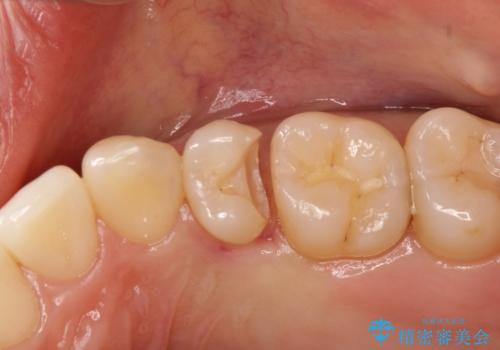

適合の良いセラミックインレー

- 定期検診して虫歯を認めたため、セラミックインレーにて修復治療を行なっております。

e-max プレスインレーにて修復治療を行っているため適合性及び審美性の高い治療を行うことができます